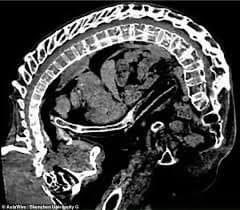

الصورة لحالة عموده الفقري قبل العملية